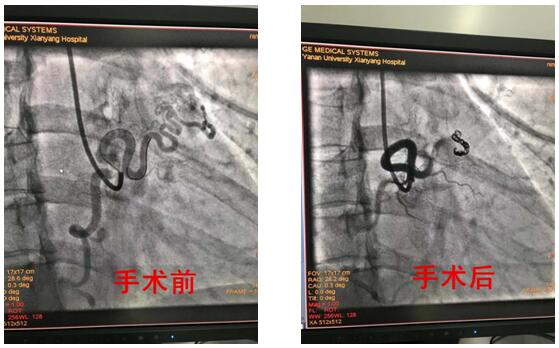

2019年8月15日對于延安大學咸陽醫院心血管病院心內VIP病區是一個不尋常的日子,因為這一天王明新主任及王顯利主任介入團隊完成了又一例右冠狀動脈---左心房瘺封堵術。

患者為39歲青年女性,反復發生心絞痛,冠脈造影示:右冠-左心房瘺道血管粗大,與右冠脈直徑相當。結合患者癥狀,考慮右冠嚴重竊血引發胸痛癥狀。心內VIP介入團隊在仔細詢問病史、認真查體及詳細的術前評估后于8月15日在導管室行彈簧圈封堵術,手術歷經2小時,術程順利,術后患者未訴不適,安返病房,術后嚴密監測血壓、心率等生命體征均平穩。

冠狀動脈瘺指冠狀動脈與心臟或大血管存在先天性異常交通,多為先天畸形,以右冠狀動脈瘺多見,占50%-60%,引入右心系統最為常見,占90%左右,以右冠狀動脈--右室瘺常見,而通入左房左室相對罕見,心內VIP病區完成的這例手術恰恰是右冠狀動脈--左房瘺。